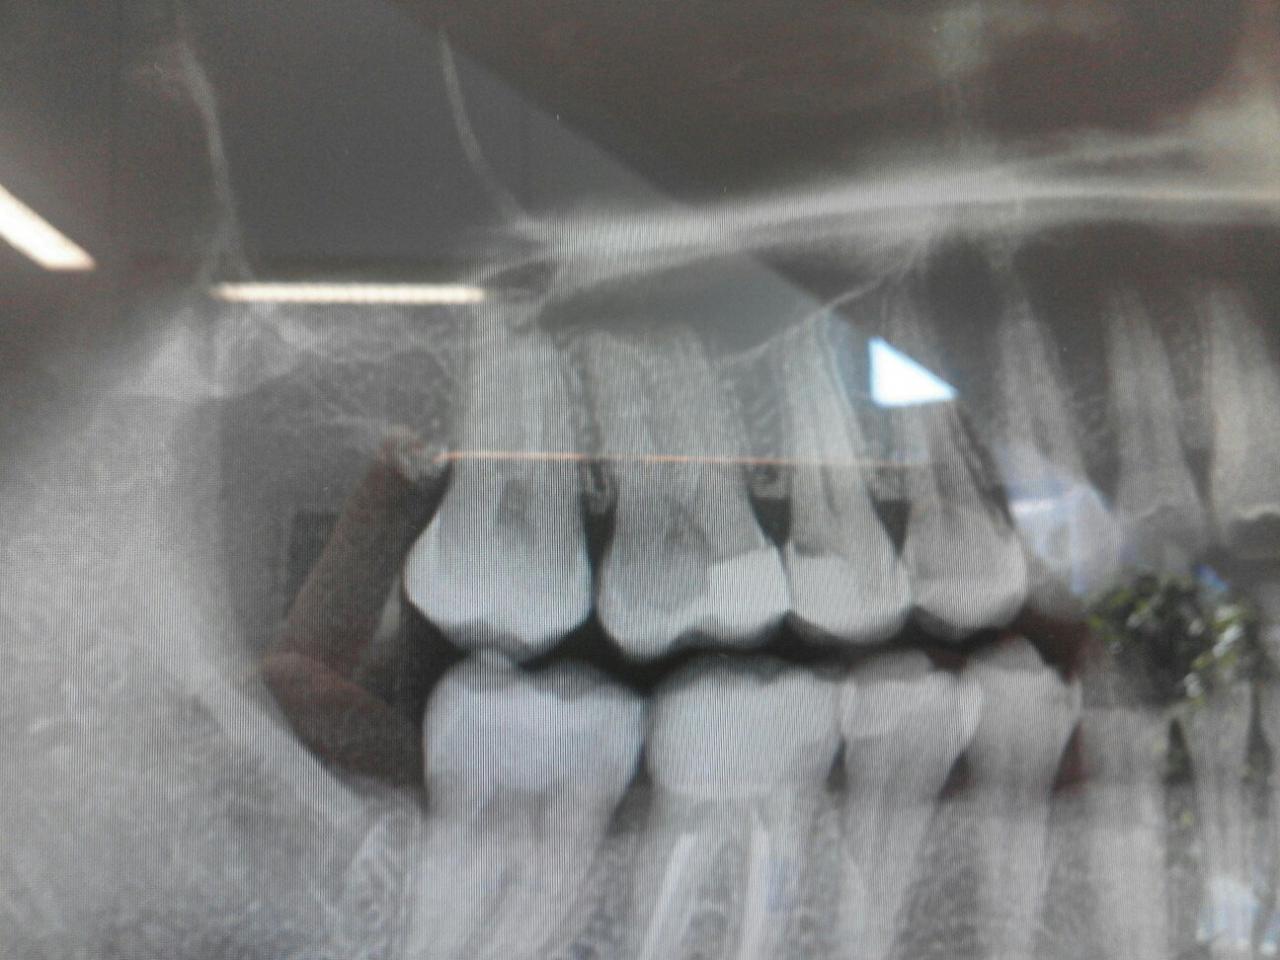

Вот на панорамном снимке хорошо видно.